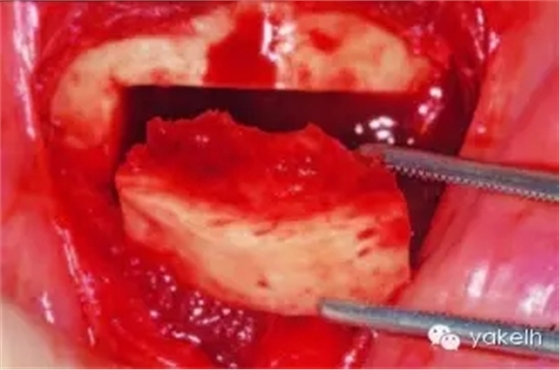

¤¤暴露頦部后,設(shè)計取骨的切口。取骨塊的大小由受區(qū)所需的骨量決定。骨切開處距離根尖以及頦孔最少應(yīng)有5mm。多數(shù)情況下,要保留下頜骨下緣以及舌側(cè)皮質(zhì)骨的完整性。唇側(cè)皮質(zhì)較厚,其內(nèi)側(cè)的松質(zhì)骨通常較致密。可以使用渦輪手機碳合金裂鉆(557號或701號)或者來復(fù)鋸將骨切開(圖13.19)。切透皮質(zhì)骨達(dá)松質(zhì)骨后,用骨鑿將骨塊移除(圖13.20)。用單面鑿沿著骨切開線輕輕敲擊,除了下頜骨下緣,將骨塊從基底部折斷。在中線處時,也可將塊狀骨分割成矩形骨塊,分段獲取。分成兩個骨塊后更容易獲取,因為可以用骨鑿將第二塊骨塊從舌側(cè)撬起。另外,移除塊狀骨后,還可使用骨刮匙、鑿子、咬骨鉗、環(huán)形鉆獲取

一些松質(zhì)骨,但是松質(zhì)骨的量十分有限。在移除塊狀骨后,可以將止血材料如膠原或明膠海綿置于松質(zhì)骨表面。當(dāng)獲取較大的骨塊時,供區(qū)應(yīng)使用骨替代材料如羥基磷灰石,來維持唇側(cè)的外形(圖13.21)。較少或者顆粒狀的骨移植時,可使用環(huán)形鉆、骨收集器、骨挖器來獲取。把骨塊植入受區(qū)后,再將供區(qū)的傷口縫合,這可以縮短取骨與植骨之間的時間。分離前庭溝切口上方的黏膜,以減少水腫和下唇運動所產(chǎn)生的張力。用可吸收縫線分層縫合前庭溝切口(圖13.22)。深層組織使用4-0可吸收線縫合,表層黏膜使用4-0鈷腸線縫合。術(shù)后使用壓力繃帶包扎頦部,以減少水腫、血腫形成及切口裂開(圖13.23)。